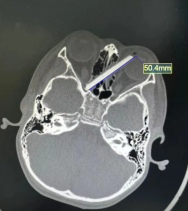

CT影像显示:断筷紧贴左眼球壁,稍有偏差就可能眼球破裂;另一端则抵住右眼的视神经管,一旦损伤视神经,随时有失明风险。